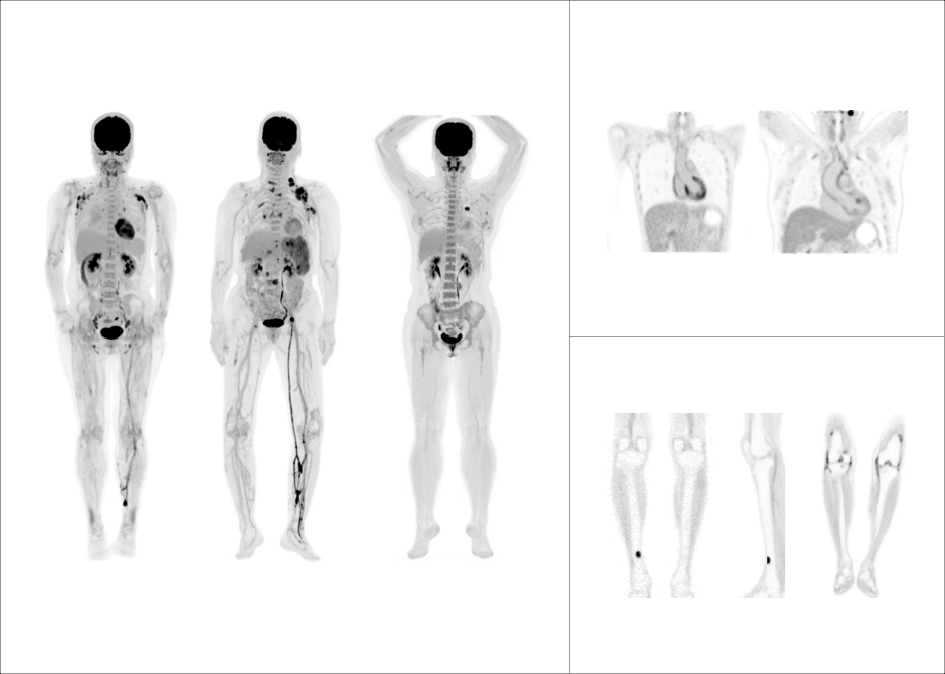

支持68Ga、 90Y、18F、82Rb、15O等不同半衰期、不同核素药物高清显像

微小淋巴结高清显像

鼻咽癌头颈部单床位大范围扫描

肺癌胸腹部单床位大范围延迟扫描

大体重患者主动脉血管结构清晰显示

68Ga-DOTA-NOC PET/CT 高清显像